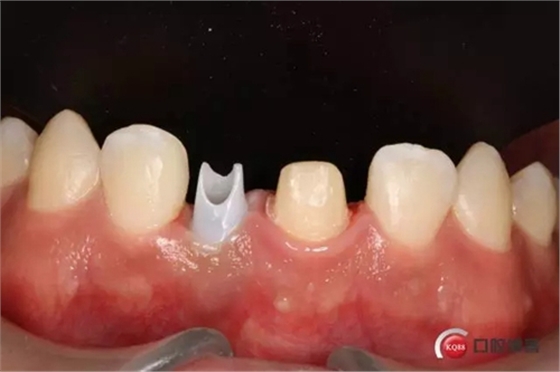

種植后修復(fù),我們要把握每一個(gè)細(xì)節(jié),比色,轉(zhuǎn)移桿的就位,我們必須把臨床做好,技工師傅才會(huì)給我們做出好的修復(fù)體,減少一些不必要的失誤,首先術(shù)前的檢查是必要一步 ,再是器械的準(zhǔn)備使我們臨床操作有條不紊,術(shù)前拍照,o-bite取咬合記錄,消毒修復(fù)術(shù)區(qū),旋出愈合基臺(tái),生理鹽水沖洗袖口,拍照袖口,安放合適轉(zhuǎn)移桿,拍X線見(jiàn)轉(zhuǎn)移桿就為良好,硅橡膠取模,術(shù)后旋回愈合基臺(tái),拍照比色。

藻酸鹽對(duì)頜取模,超硬石膏灌注。發(fā)加工廠,與技工溝通注意事項(xiàng),等修復(fù)體做好后,檢查模型。是否就位,是否密合,預(yù)約患者復(fù)診戴牙,消毒修復(fù)區(qū),旋出愈合基臺(tái),定位器指導(dǎo)安放修復(fù)基臺(tái),試戴冠,調(diào)磨鄰接及 咬合至合適,拋光,患者滿意,加力扳手加力至30N,拍X片見(jiàn)就位良好,特芙蓉及暫封膏封中央螺絲孔,聚羧酸鋅粘固劑粘固,或是樹(shù)脂水門汀粘固,清理多余粘結(jié)劑,光固化樹(shù)脂封螺絲孔,拋光。術(shù)后注意隨訪。